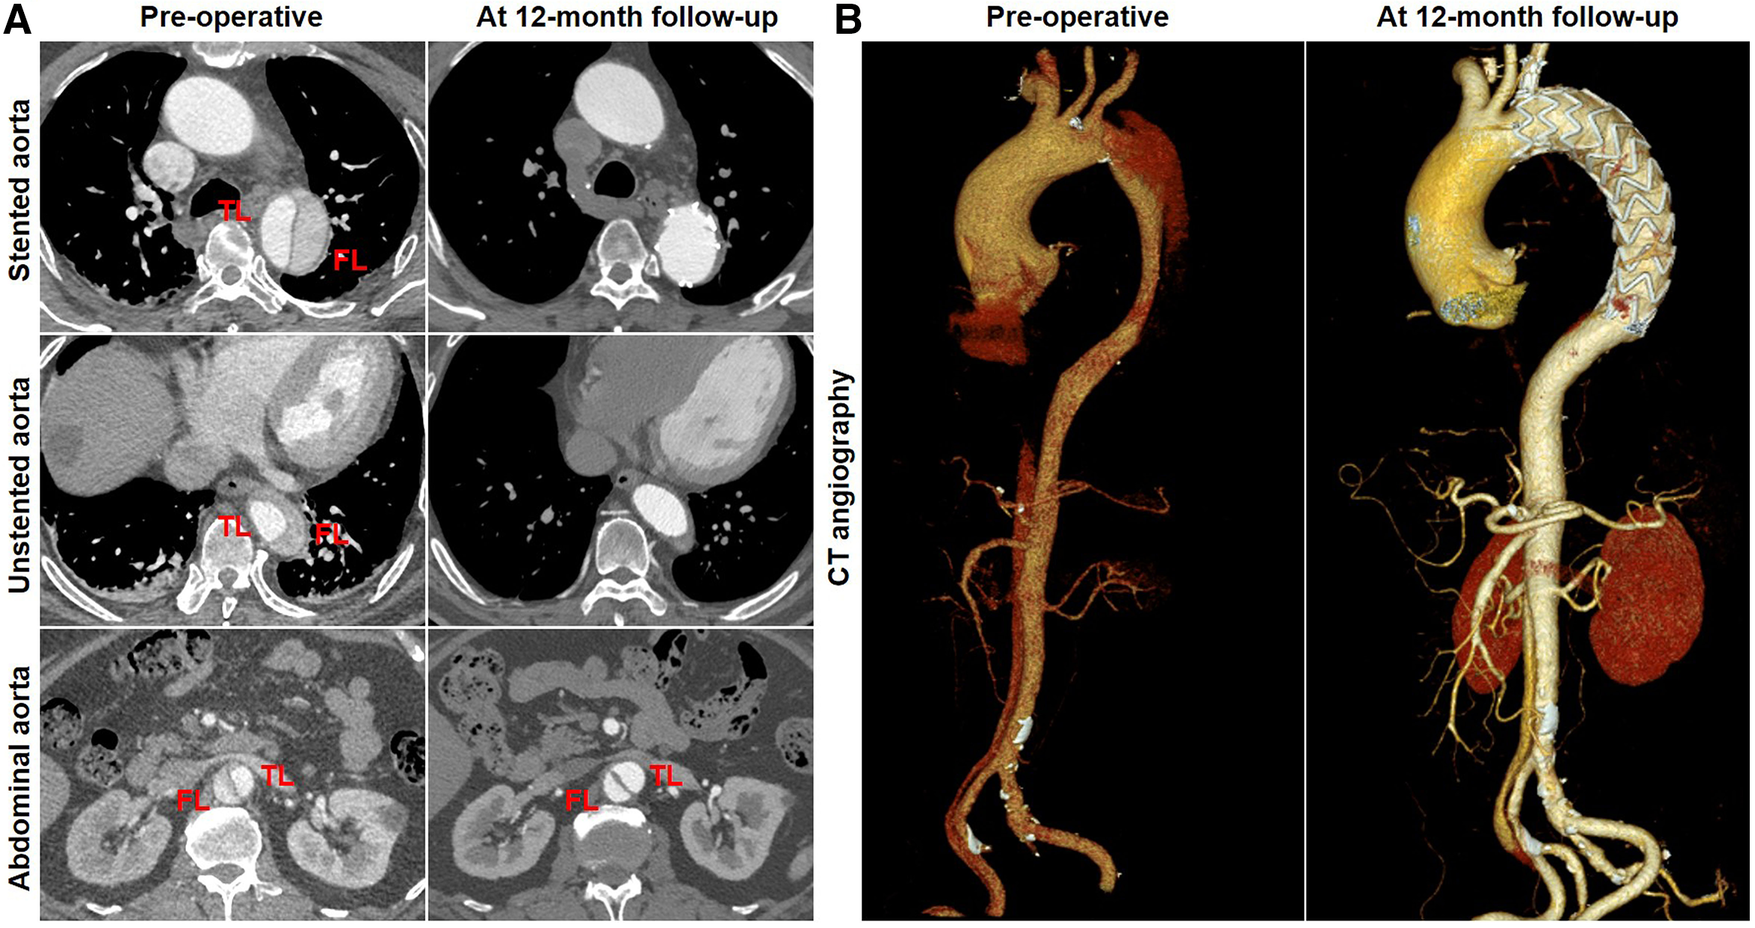

Aortic remodeling: representative CTA preoperatively and at follow-up

Favorable aortic remodeling was explained as FL thrombosis, FL obliteration, TL enlargement, and transaortic stabilization. A 66-year-old woman was diagnosed with TBAD, underwent TEVAR with the Castor stent graft, and completed a 12-month CT follow-up. Cross-sectional and three-dimensional reconstruction CT images are illustrated in Figures 4A,B, respectively. At 12 months following TEVAR, FL was entirely thrombosed and regressed, and TL was mostly recovered over the whole stented and unstented thoracic aorta. FL was patent but did not enlarge, and TL was relatively stabilized over the abdominal aorta 12 months after TEVAR.

Figure 4

Favorable aortic remodeling after TEVAR with the Castor stent graft. (A) Cross-sectional CT images were obtained from three aortic segments. At the 12-month follow-up, TL enlargement, FL thrombosis and obliteration, and transaortic stabilization were observed over the stented and unstented thoracic aorta; patent FL was stable at the abdominal aorta after TEVAR. (B) Three-dimensional reconstructed CT images exhibited excellent remodeling at the stented and unstented aorta and stable configuration at the abdominal aorta. CT, computed tomography; FL, false lumen; TEVAR, thoracic endovascular aortic repair; TL, true lumen.